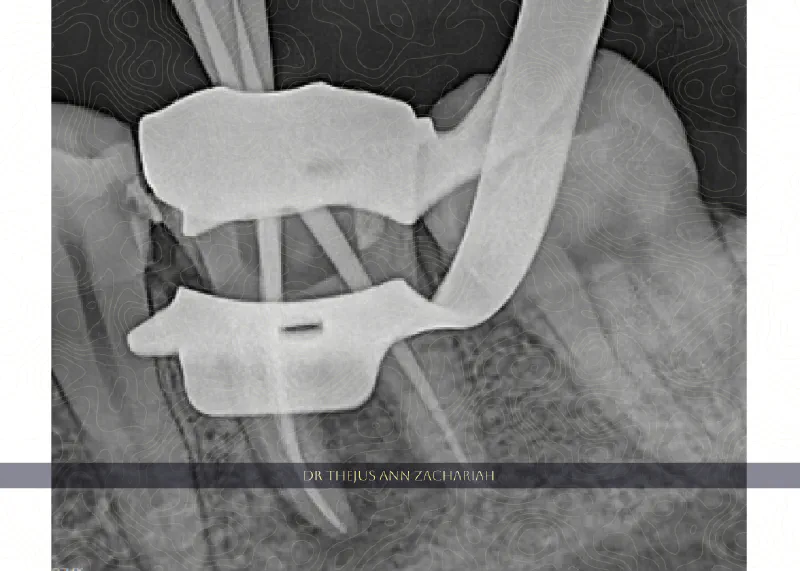

Root Canal Treatment

RCT - 48RCT - 48 RCT - Upper Molar With MB2 - 16RCT - Upper Molar With MB2 - 16 RCT - Through Crown 36RCT - Through Crown 36